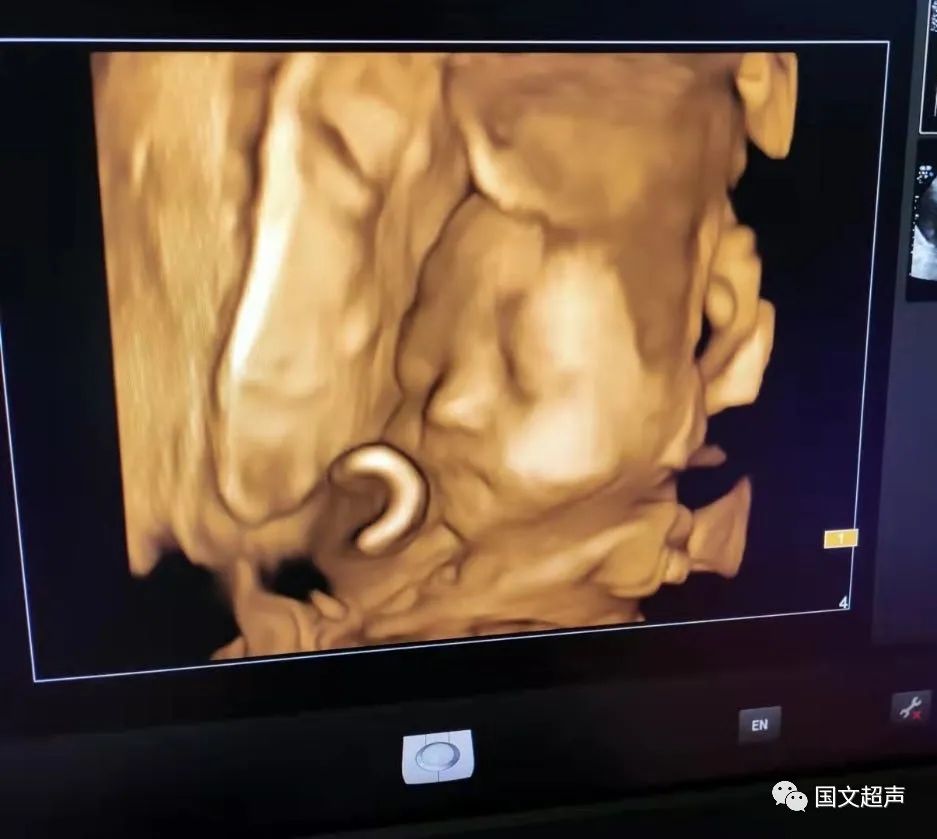

一.飛利浦EPIQ7高端四維彩超

我院目前使用的是飛利浦EPIQ7高端四維彩超,它擁有高品質自動成像分析技術,分辨率及清晰度高,可以較清晰的顯示宮內胎兒的生長發(fā)育情況,為診斷胎兒先天性畸形,如唇裂、脊柱裂、顱腦發(fā)育異常、骨骼發(fā)育異常、心血管畸形等提供準確的科學依據。